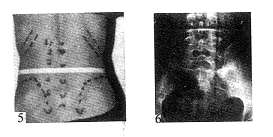

对髂骨的形态和其高度对L5~S1椎间盘的相对关系的研究尚未见记载。1992年3月发现第1例直角髂嵴的病例〔12〕,其髂骨嵴不是通常的“S”状浅弧形,而是自髂骨后上棘向上接近垂直向外侧倾斜约15°,升至L4~5椎间隙平面或以上,呈直角转向前外方,略向下斜至髂前上棘。此种直角髂嵴 (right-angled iliac crest)其后1/4段接近垂直,与后正中线距离<5cm(图5、6)。在此狭窄的范围内,无论是通常后外侧途径(距离后正中线8~10cm),还是中间位后外侧途径(距后正中线6~8cm),L5~S1节段自然成为非适应证。我们在347例统计中发现10例直角髂嵴 ,占2.88%〔10〕,其髂翼偏高者居多数,Jacobys线在L4~5椎间隙平面以上者7例。所幸者,直角髂嵴与高髂翼同样具有一种倾向,男多于女,L5~S1椎间盘处于骨盆相对较深位置,因此发生椎

图5 直角髂嵴 图6直角髂嵴X线正位片(髂嵴后1/4部垂直升至L4椎体上缘,呈直角转向前外方与后正中线距离仅4.5cm

间盘突出的机率甚少。在临床上10余年中腰椎间盘突出症兼有直角髂嵴者仅遇4例,其突出节段均不在L5~S1椎间盘。